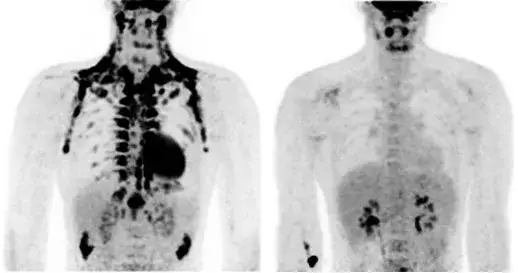

Badanie PET (pozytonowa tomografia emisyjna) to kluczowa metoda diagnostyczna, która pozwala na wczesne wykrywanie nowotworów oraz oceny ich zaawansowania. Dla pacjentów w Polsce, korzystających z Narodowego Funduszu Zdrowia (NFZ), ważne jest, aby wiedzieć, gdzie można uzyskać najszybsze terminy na takie badanie. W tym artykule przedstawimy najlepsze lokalizacje, gdzie czas oczekiwania na badanie PET jest najkrótszy, a także omówimy proces rejestracji oraz wymagane dokumenty.

Oprócz ogólnych wskazań, NFZ określa również konkretne sytuacje, w których badanie PET jest zalecane. Należą do nich między innymi: ocena skuteczności leczenia nowotworów, wykrywanie przerzutów oraz różnicowanie zmian nowotworowych od zmian łagodnych. Spełnienie tych kryteriów jest niezbędne, aby pacjent mógł skorzystać z szybkich terminów badania PET w ramach NFZ, co jest szczególnie istotne dla osób z pilnymi potrzebami diagnostycznymi.

W przypadku pacjentów onkologicznych, NFZ zaleca wykonanie badania PET w kilku specyficznych sytuacjach. Badanie to jest wskazane w celu oceny odpowiedzi na leczenie nowotworów, identyfikacji przerzutów oraz oceny wznowy choroby. Dodatkowo, pacjenci z podejrzeniem nowotworów, którzy wymagają dalszej diagnostyki, również mogą skorzystać z tego badania. Dzięki tym wskazaniom, pacjenci mają szansę na szybszą i skuteczniejszą diagnostykę, co może znacząco wpłynąć na ich dalsze leczenie.